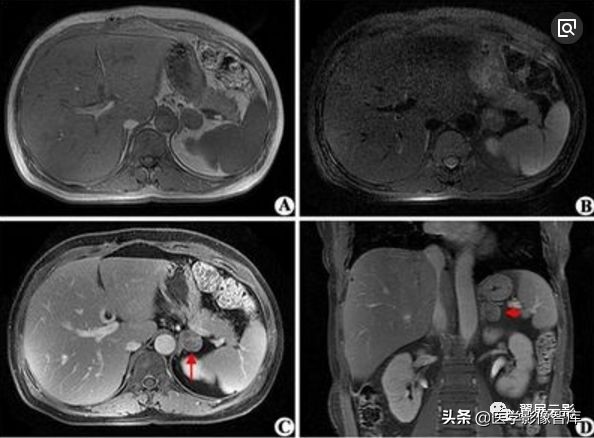

多囊肾

本病常合并多囊肝,此为先天性常染色体显性遗传性疾病,多数学者认为多囊肝是在多囊肾的基础上基因突变的结果,并定位于16号染色体上,也有学者认为该病是由于胚胎发育不良所导致,于胚胎早期管道形成时排列失常,造成无数迷管,于胚胎晚期未退化,且逐渐扩张成囊,成多发性囊肿病,根据发病年龄的不同,将其分为儿童型和成人型,本病多发生于双侧肾脏,可继发感染,结石以及囊内出血和囊壁钙化,也可以恶变,并有阻塞性黄疸及合并皮下囊肿的报道,临床上早期无症状,就诊时肾脏功能已经不同程度受损,肝功能受损程度较轻。

MRI表现为双肾增大和分叶状轮廓,多发囊肿多数为长T1长T2信号,出血性囊肿可为短T1长T2信号或长T1短T2信号,增强扫描所有病灶均不强化,应同时观察合并的多囊肝及胰脾多发囊肿。